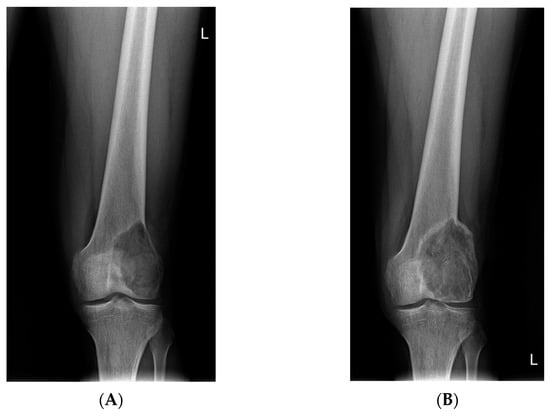

- Van Langevelde, K.; McCarthy, C.L. Radiological findings of denosumab treatment for giant cell tumours of bone. Skelet. Radiol. 2020, 49, 1345–1358. [Google Scholar] [CrossRef] [PubMed]

- Oguro, S.; Okuda, S.; Sugiura, H.; Matsumoto, S.; Sasaki, A.; Susa, M.; Morioka, H.; Jinzaki, M. Giant Cell Tumors of the Bone: Changes in Image Features after Denosumab Administration. Magn. Reson. Med. Sci. 2018, 17, 325–330. [Google Scholar] [CrossRef]

- Hakozaki, M.; Tajino, T.; Yamada, H.; Hasegawa, O.; Tasaki, K.; Watanabe, K.; Konno, S. Radiological and pathological characteristics of giant cell tumor of bone treated with denosumab. Diagn. Pathol. 2014, 9, 111. [Google Scholar] [CrossRef]